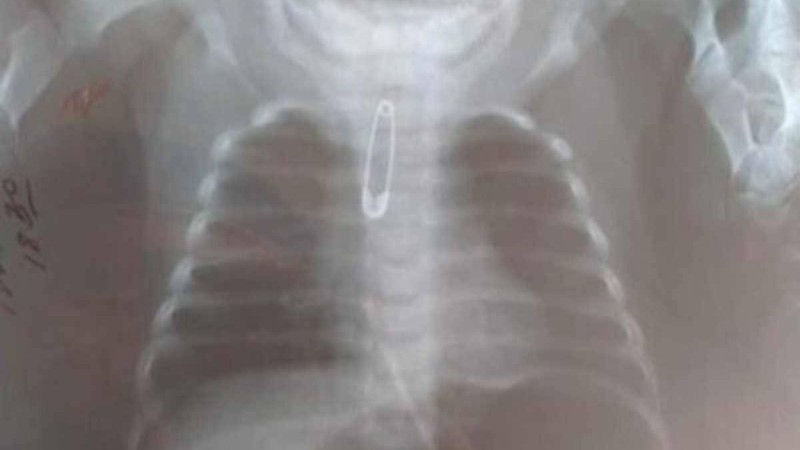

Шымкентте үш айлық баланың ішінен түйреуіш шықты Шымкент қаласындағы балалар клиникалық ауруханасына тыныс алу жолында бөгде зат бар... 16 сәуір 2021 • Шоу-бизнес